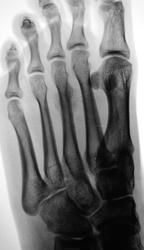

Травма. Пациент направлен на рентгенографию переднего отдела стопы.

Очень похоже на Дойчлендера.

Да, очень похоже.

Слишком размытая картина для перегрузочной, а вот на нечто нехорошее очень похоже.

Я тоже за стресс-перелом - типичная локализация, виден дефект в кортикальном слое, периостальная реакция

Но не свежая, если есть элементы склерозирования. А боли сильные?

Боли умеренные, ходит хромая.

Конечно, я может быть умничаю, но для окончательного диагноза надо "резать" -либо КТ, либо обычные томограммы, МРТ (?). Кость-то представляется более-менее приличной, но мягкие ткани-то мы не видим.